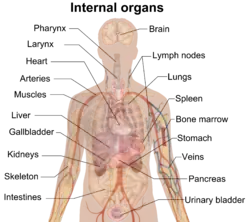

Author: David Richfield

This is a gallery of images contributed to Wikimedia projects by David Richfield by 2014